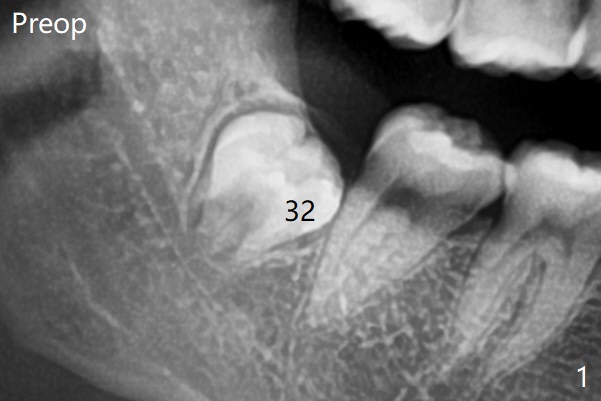

原来右下牙槽窝放置骨胶原塞(Osteogen Plug),而左下胶原塞。

塞的密度       Last     Next   智齿拔除